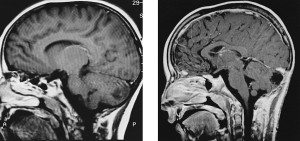

Le immagini di risonanza magnetica encefalica e angio risonanza cui la bambina viene sottoposta mostrano una realtà molto differente: non si tratta di lievi anomalie ma di una disfunzione che riguarda quasi un emisfero intero. La risonanza magnetica encefalica rivela infatti una grande cisti poroencefalica che coinvolge praticamente tutto l’emisfero di sinistra con risparmio esclusivamente del nastro corticale in regione fronto-basale, temporale anteriore e temporale mesiale, talamo e nuclei della base. L’esame di angio risonanza dell’encefalo e dei vasi al collo evidenzia una brusca, netta riduzione di flusso sia dell’arteria cerebrale media sia dell’arteria cerebrale posteriore di sinistra e coesistente ipoplasia del tratto a1 dell’arteria cerebrale anteriore.

Nonostante il vistoso danno cerebrale, lo sviluppo neurologico è stato relativamente preservato: la paziente infatti presenta solo una lieve spasticità all’emisoma destro, un lieve disturbo dell’articolazione della parola e capacità di comprensione adeguate all’età.